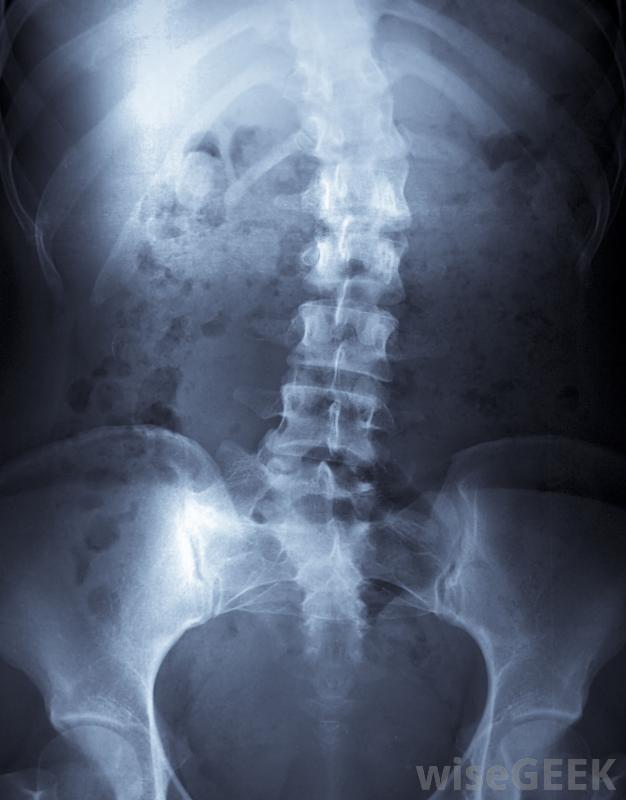

NF1患者在儿童时期也可能有脊柱侧凸或其他骨畸形神经纤维瘤病有两种类型,NF1是较不严重的一种,每4种中就有一种发生,大约有000个婴儿。由于皮肤上有"咖啡汁"斑点,通常会被早期诊断出来。神经纤维瘤通常很小,如果造成美容缺陷或压迫重要器官,可以将其切除

患有神经纤维瘤病的儿童的父母如果肿瘤明显生长,应立即联系儿科医生儿童脊柱侧凸或其他骨畸形。然而,大多数I型神经纤维瘤病患者将过着正常的生活,许多人几乎没有,如果有任何问题,与该疾病有些孩子小时候会癫痫发作,或者可能会有语言障碍,但是药物和语言治疗已经被证明对帮助这些孩子正常生活非常有效。2型神经纤维瘤病是另一回事。大约每5万个婴儿中就有一个会受到NF2的影响,而且每一个级别都会更严重,患者可能会在耳朵的神经上长出肿瘤,最终导致耳聋。肿瘤也可能出现在脊髓或大脑上。幸运的是,只有大约3%到5%的神经纤维瘤会癌变。然而,家长需要对孩子的肿瘤进行检查,如果其中一个肿瘤有明显的生长,父母应该立即打电话给儿科医生。患有NF1并一直保持健康到成年的孩子有很好的机会保持健康并过上正常的寿命。我们提供支持小组,既适用于神经纤维瘤病患者,也适用于患有该病的儿童。